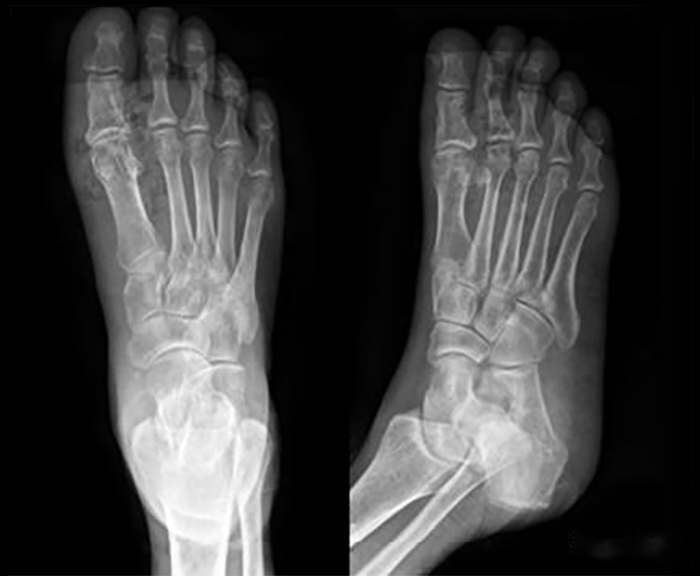

代表病例一56岁女性患者,患者入院诊断:右足糖尿病足(wagner 3级),中度贫血,脓毒血症,低蛋白血症。患者入院后完善其相关检查,积极抗感染、控制血糖及改善内环境,完善下肢血管造影提示胫前动脉闭塞。经完善术前准备后,予患者行右胫骨 Ilizarov 横向骨搬移 + 清创术。术后常规创面换药及定期复查 X线片,骨搬移术后 4 个月患者左下肢伤口愈合,患肢颜色及皮温改善。